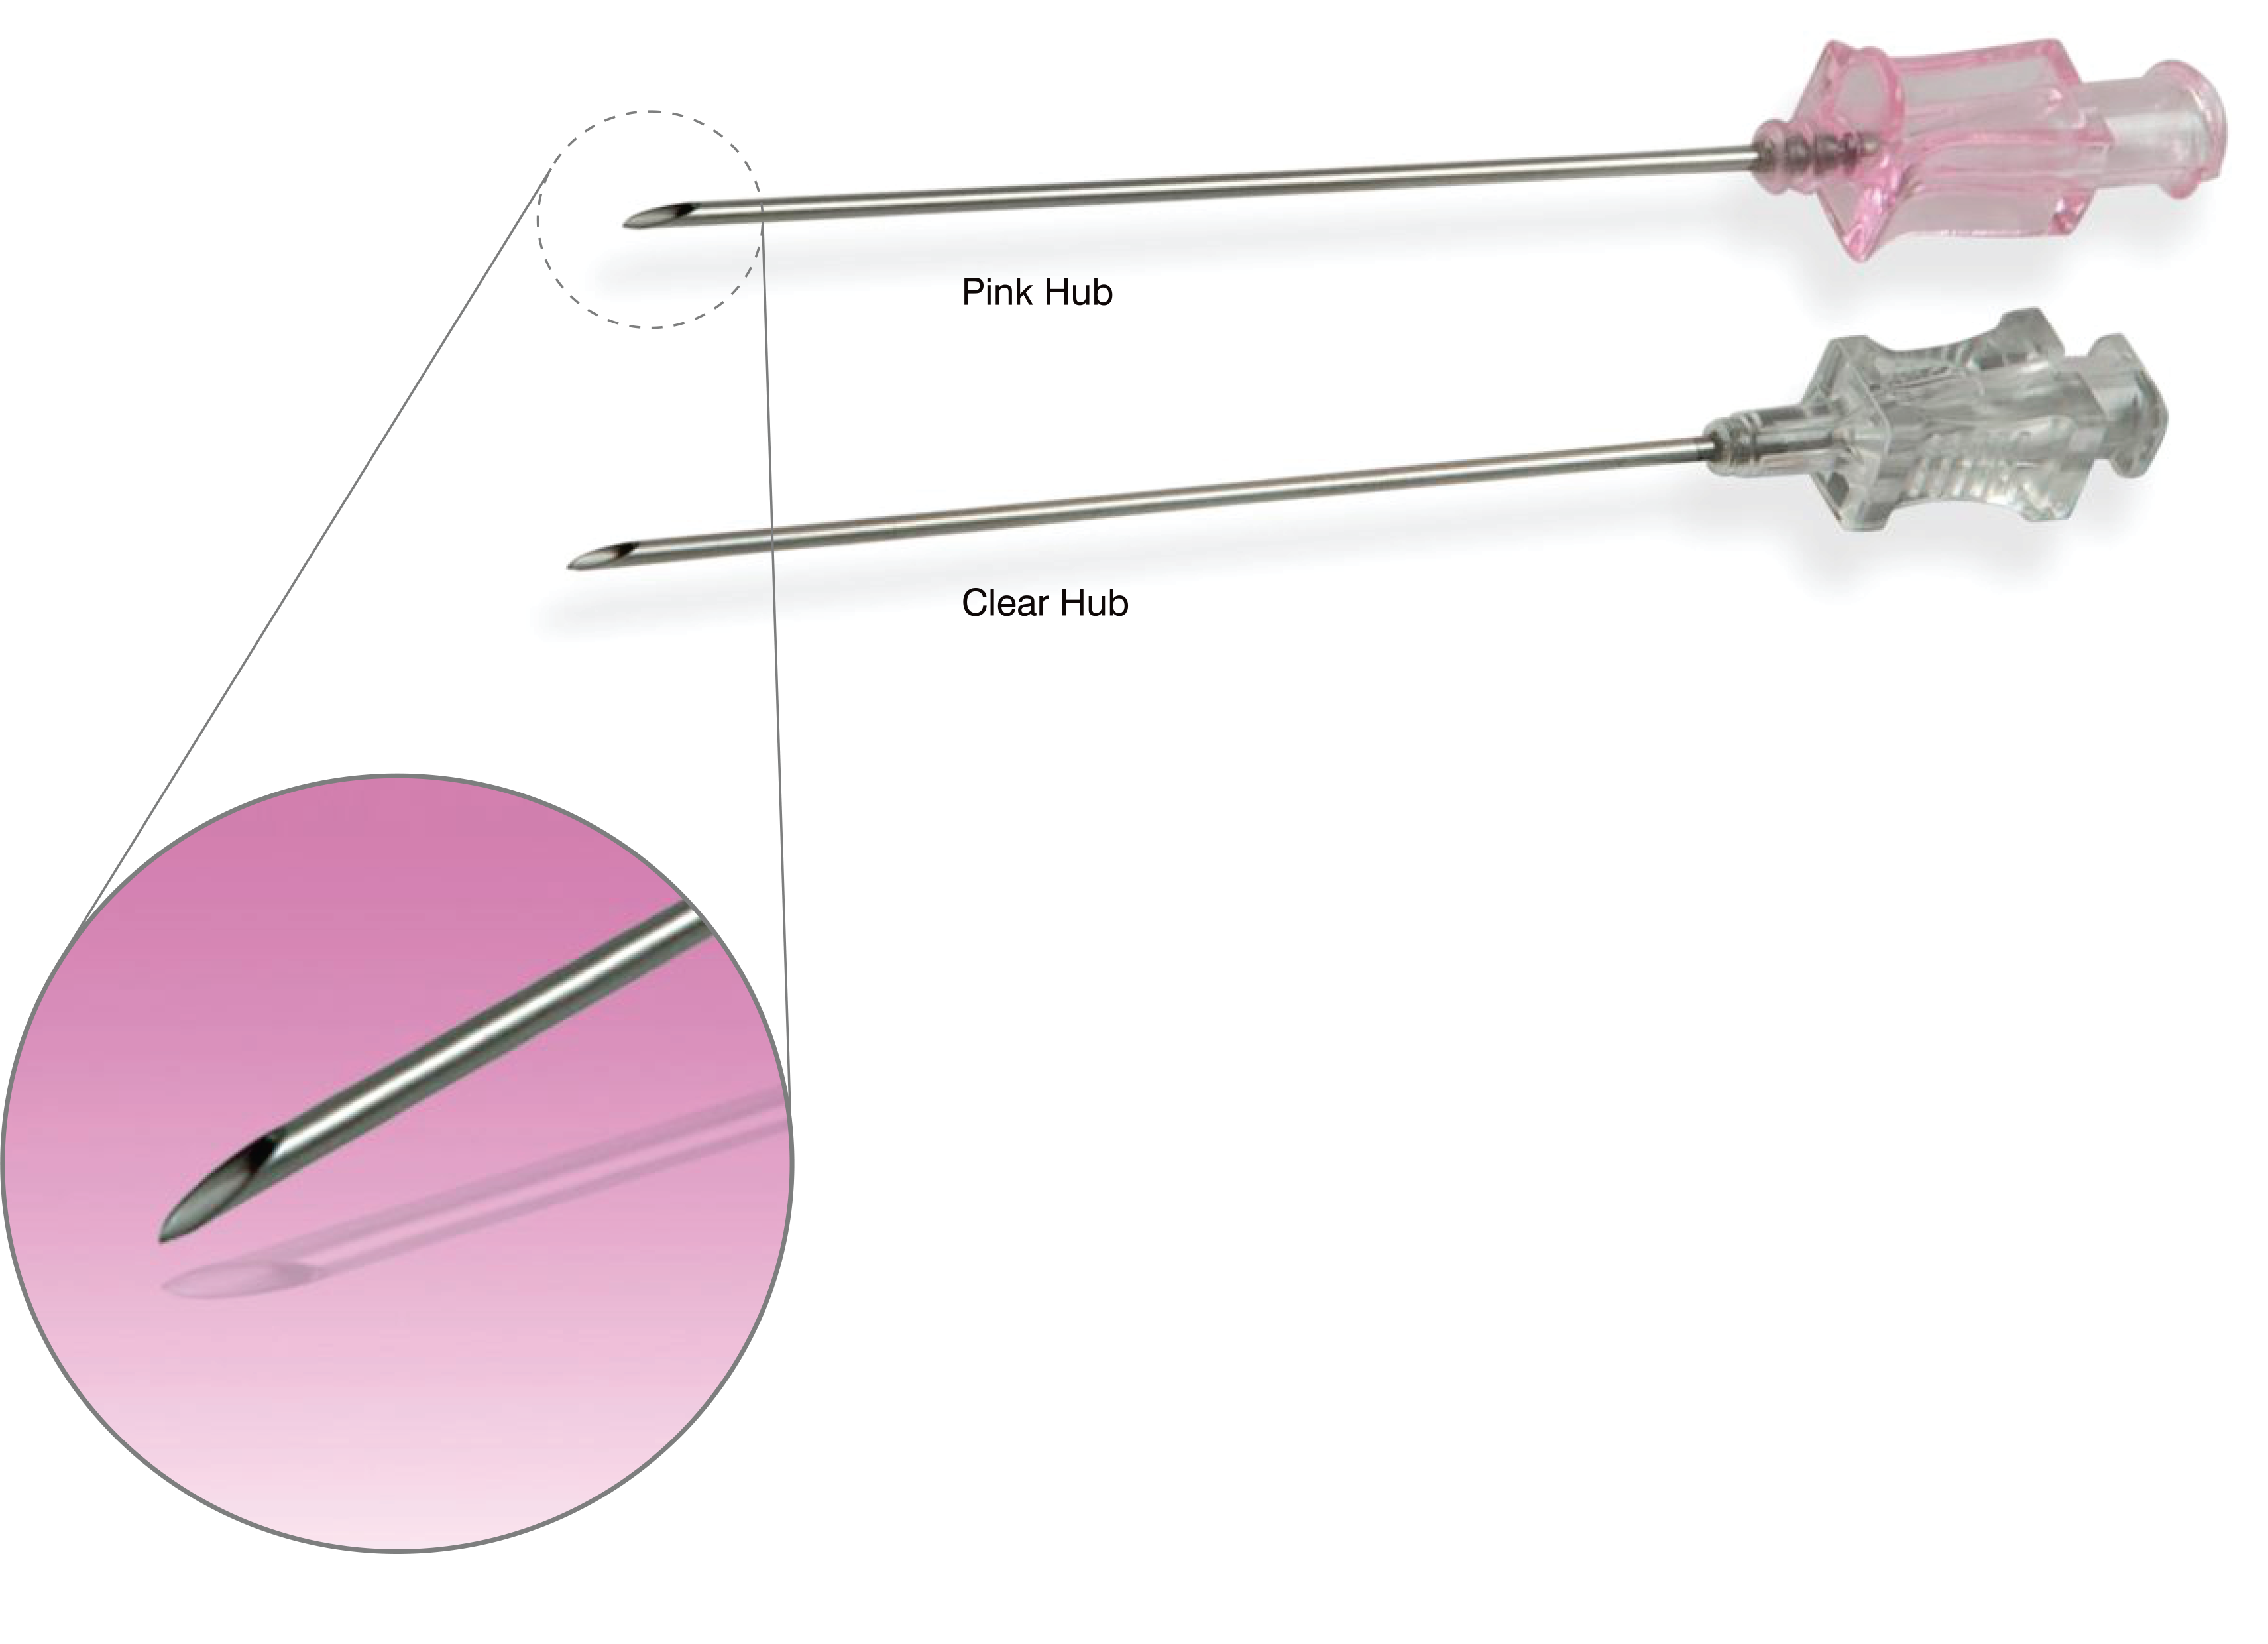

Introducer Needle

Puncture needle is used for gaining access in to the artery for introduction of all the devices that are subsequently going to be used in angiography & angioplasty.

It has unique diamond shaped back cut at the tip.

Specifications

- Unique back cut technology and have a diamond shaped in the front to give the clear puncture.

- Thinner wall thickness, large inner diameter.

- High quality medical grad 304 stainless steel.

- Sharp needle tip.